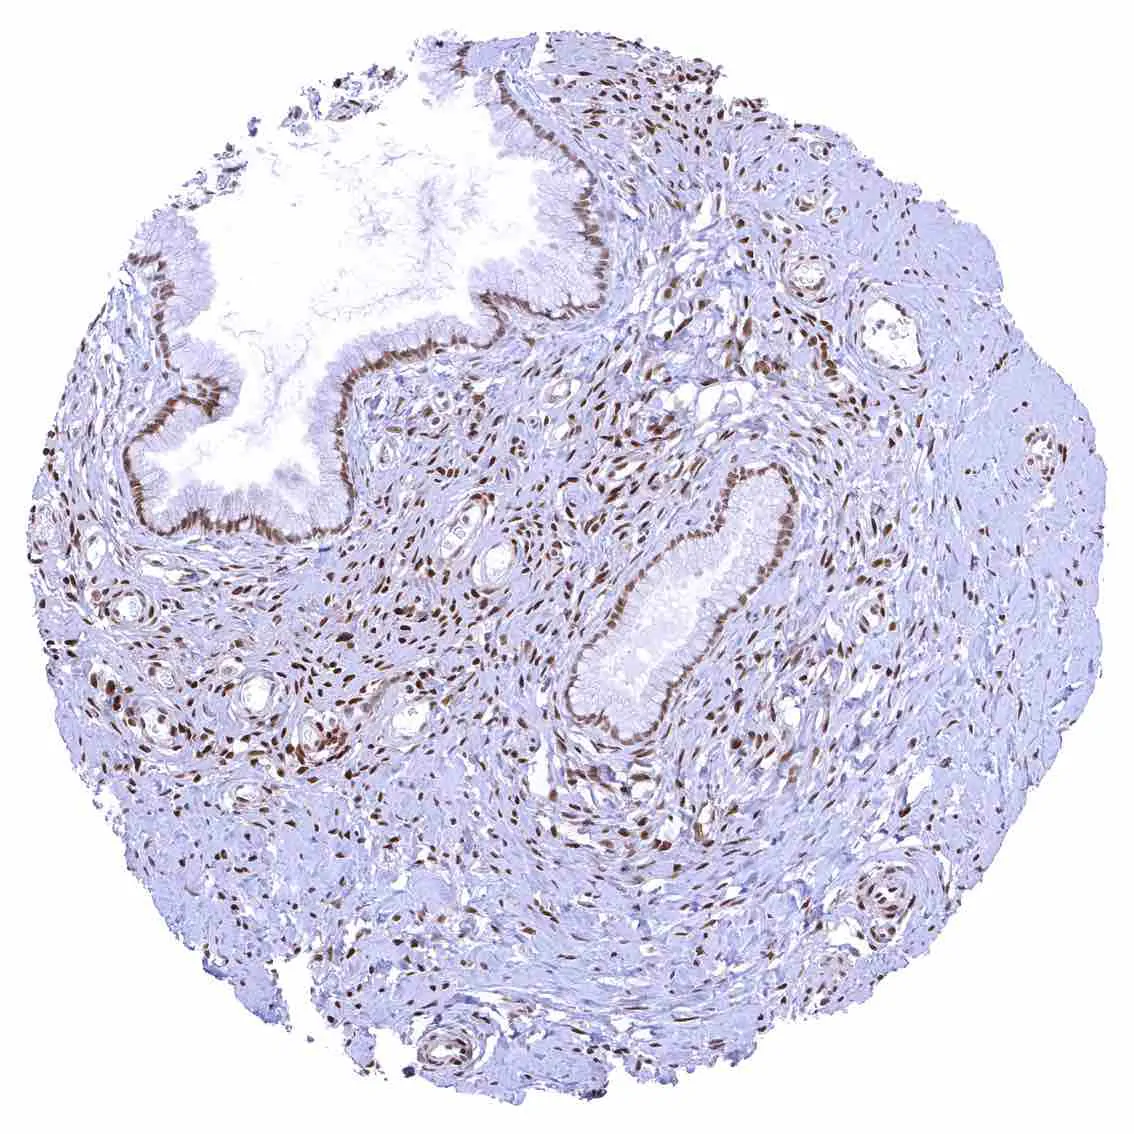

Uterus, endocervix – Nuclear p27 staining is variable in the endocervix. It is positive in all epithelial cells in this sample.

Uterus, endocervix